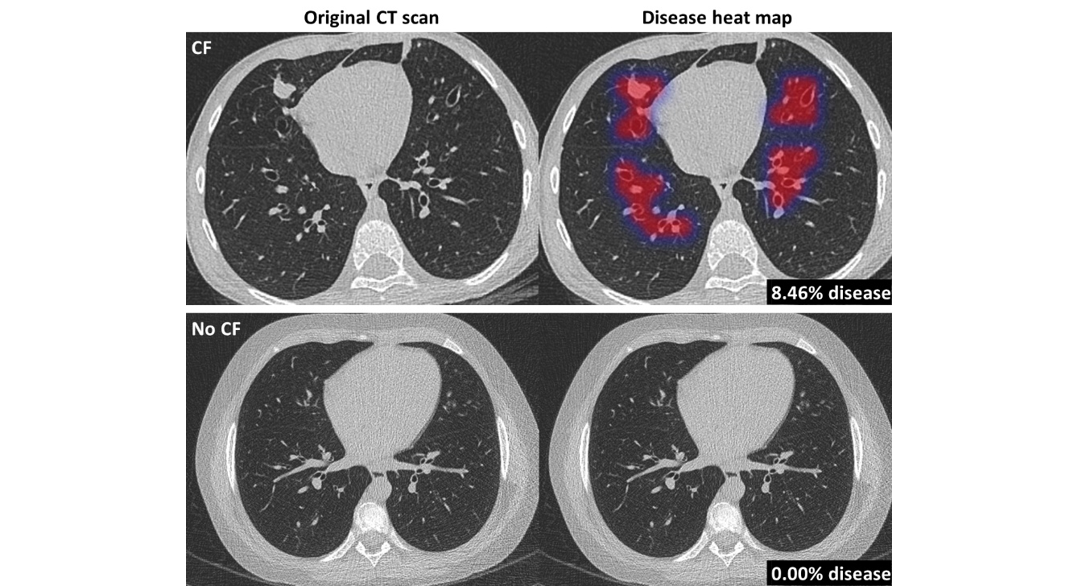

Thirona developed an AI algorithm that revolutionizes cystic fibrosis (CF) care.